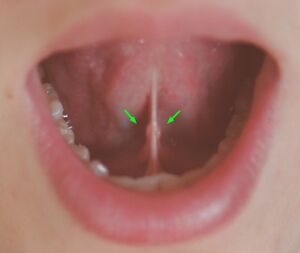

Sublingual caruncles highlighted on either side of the frenulum

Secretions are delivered into the submandibular duct on the deep portion after which they hook around the posterior edge of the mylohyoid muscle and proceed on the superior surface laterally. The excretory ducts are then crossed by the lingual nerve, and ultimately drain into the sublingual caruncles – small prominences on either side of the lingual frenulum along with the major sublingual duct. The gland can be bilaterally palpated (felt) inferior and posterior to the body of the mandible, moving inward from the inferior border of the mandible near its angle with the head tilted forwards.[4]

Submandibular gland papilla

The terminal part of the submandibular (Wharton's) duct is located in the mouth floor and opens as an orifice of the submandibular duct papilla. The position of the duct and its 0.5–1.5 mm wide ostium is invariably symmetric, but quite unpredictable; consequently, submandibular duct papilla can occasionally be challenging to recognize. Based on the macroscopic appearance of the papillae and sialendoscopic approach, Anicin et al. described four different types of submandibular gland papillae (types A, B, C, and D). [5]